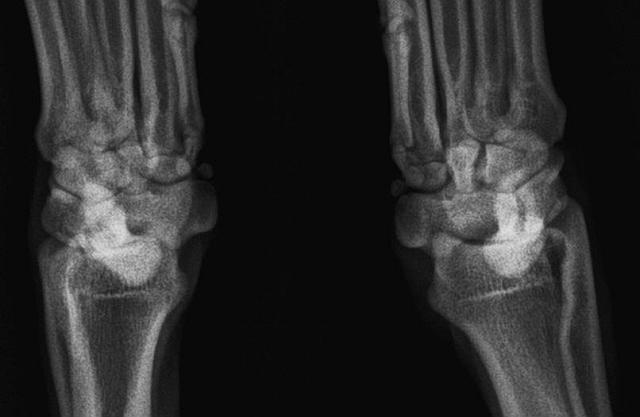

Ich bin nach dieser ersten Diagnose mit Iuju auf Empfehlung anderer Rennhundebesitzer in die Niederlande zu Dr. Dijkshoorn gefahren, um Iuju untersuchen und gegebenenfals operieren zu lassen. Glücklicherweise meinte Dr. Dijkshoorn bereits nach der manuellen Untersuchung, dass wohl die Bänder ordentlich überdehnt sind, aber sich sonst alles intakt anfühlt. Den Stein, der mir da von der Seele plumpste, muss man wohl bis nach Hause gehört haben. Drei neue Röntgenbilder in verschiedenen Ebenen bestätigten seine Aussage, gerissen ist nix.

Also gab es eine Injektion ins Gelenk, und die strikte Anweisung, 3 Wochen Leinenzwang einzuhalten und in der vierten Woche mit der Aktivierung zu beginnen.Dr. Dijkshoorn meinte sogar, dass Iuju zum Ende der Saison wieder Rennen laufen könnte. Warten wir es mal ab.